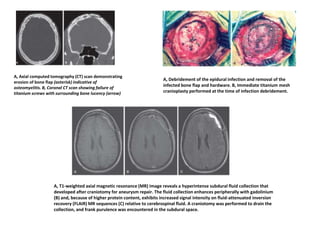

A, Axial computed tomography (CT) scan demonstrating

erosion of bone flap (asterisk) indicative of

osteomyelitis. B, Coronal CT scan showing failure of

titanium screws with surrounding bone lucency (arrow)

A, Debridement of the epidural infection and removal of the

infected bone flap and hardware. B, Immediate titanium mesh

cranioplasty performed at the time of infection debridement.

A, T1-weighted axial magnetic resonance (MR) image reveals a hyperintense subdural fluid collection that

developed after craniotomy for aneurysm repair. The fluid collection enhances peripherally with gadolinium

(B) and, because of higher protein content, exhibits increased signal intensity on fluid-attenuated inversion

recovery (FLAIR) MR sequences (C) relative to cerebrospinal fluid. A craniotomy was performed to drain the

collection, and frank purulence was encountered in the subdural space.